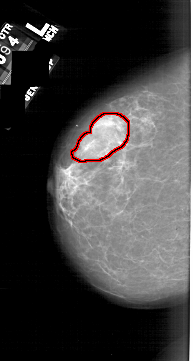

A_1740_1.RIGHT_MLO

FILE: A_1740_1.RIGHT_MLO.OVERLAY

TOTAL_ABNORMALITIES 1

ABNORMALITY 1

LESION_TYPE CALCIFICATION TYPE PLEOMORPHIC DISTRIBUTION CLUSTERED

ASSESSMENT 4

SUBTLETY 2

PATHOLOGY BENIGN

TOTAL_OUTLINES 1

BOUNDARY